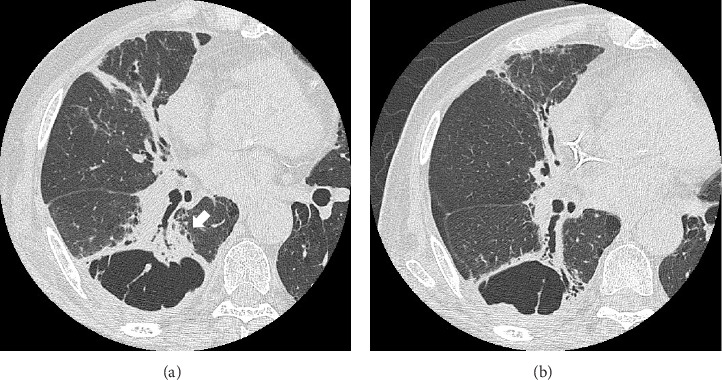

小细胞肺癌(SCLC)合并囊性气隙是罕见的。我们描述的情况下,68岁的男子谁被转介到我们医院,因为在胸部x线检查发现囊性病变。最初的计算机断层扫描显示右下叶膈旁肺气肿引起的小结节邻近囊性空域。组织病理学检查淋巴结病变提示SCLC。化疗后,复发表现为厚壁囊性空腔,囊肿壁有外生结节,类似肺炎。额外的化疗,而不是抗生素治疗,导致壁厚和结节的减少。该病例强调了对抗生素治疗的无反应性,特别是在具有危险因素的患者中,突出了可能延迟及时癌症治疗的诊断陷阱。

Small-cell lung carcinoma (SCLC) associated with cystic airspaces is rare. We describe the case of a 68-year-old man who was referred to our hospital because of a cystic lesion detected on chest radiography. Initial computed tomography revealed a small nodule abutting the cystic airspace due to paraseptal emphysema in the right lower lobe. Histopathological examination of lymphadenopathy indicated SCLC. Postchemotherapy, recurrence appeared as a thick-walled cystic airspace with an exophytic nodule along the cyst wall, mimicking pneumonia. Additional chemotherapy, but not antibiotic therapy, led to a reduction in the wall thickness and nodules. This case emphasizes unresponsiveness to antibiotic therapy, especially in patients with risk factors, highlighting the diagnostic pitfall that may delay timely cancer treatment.